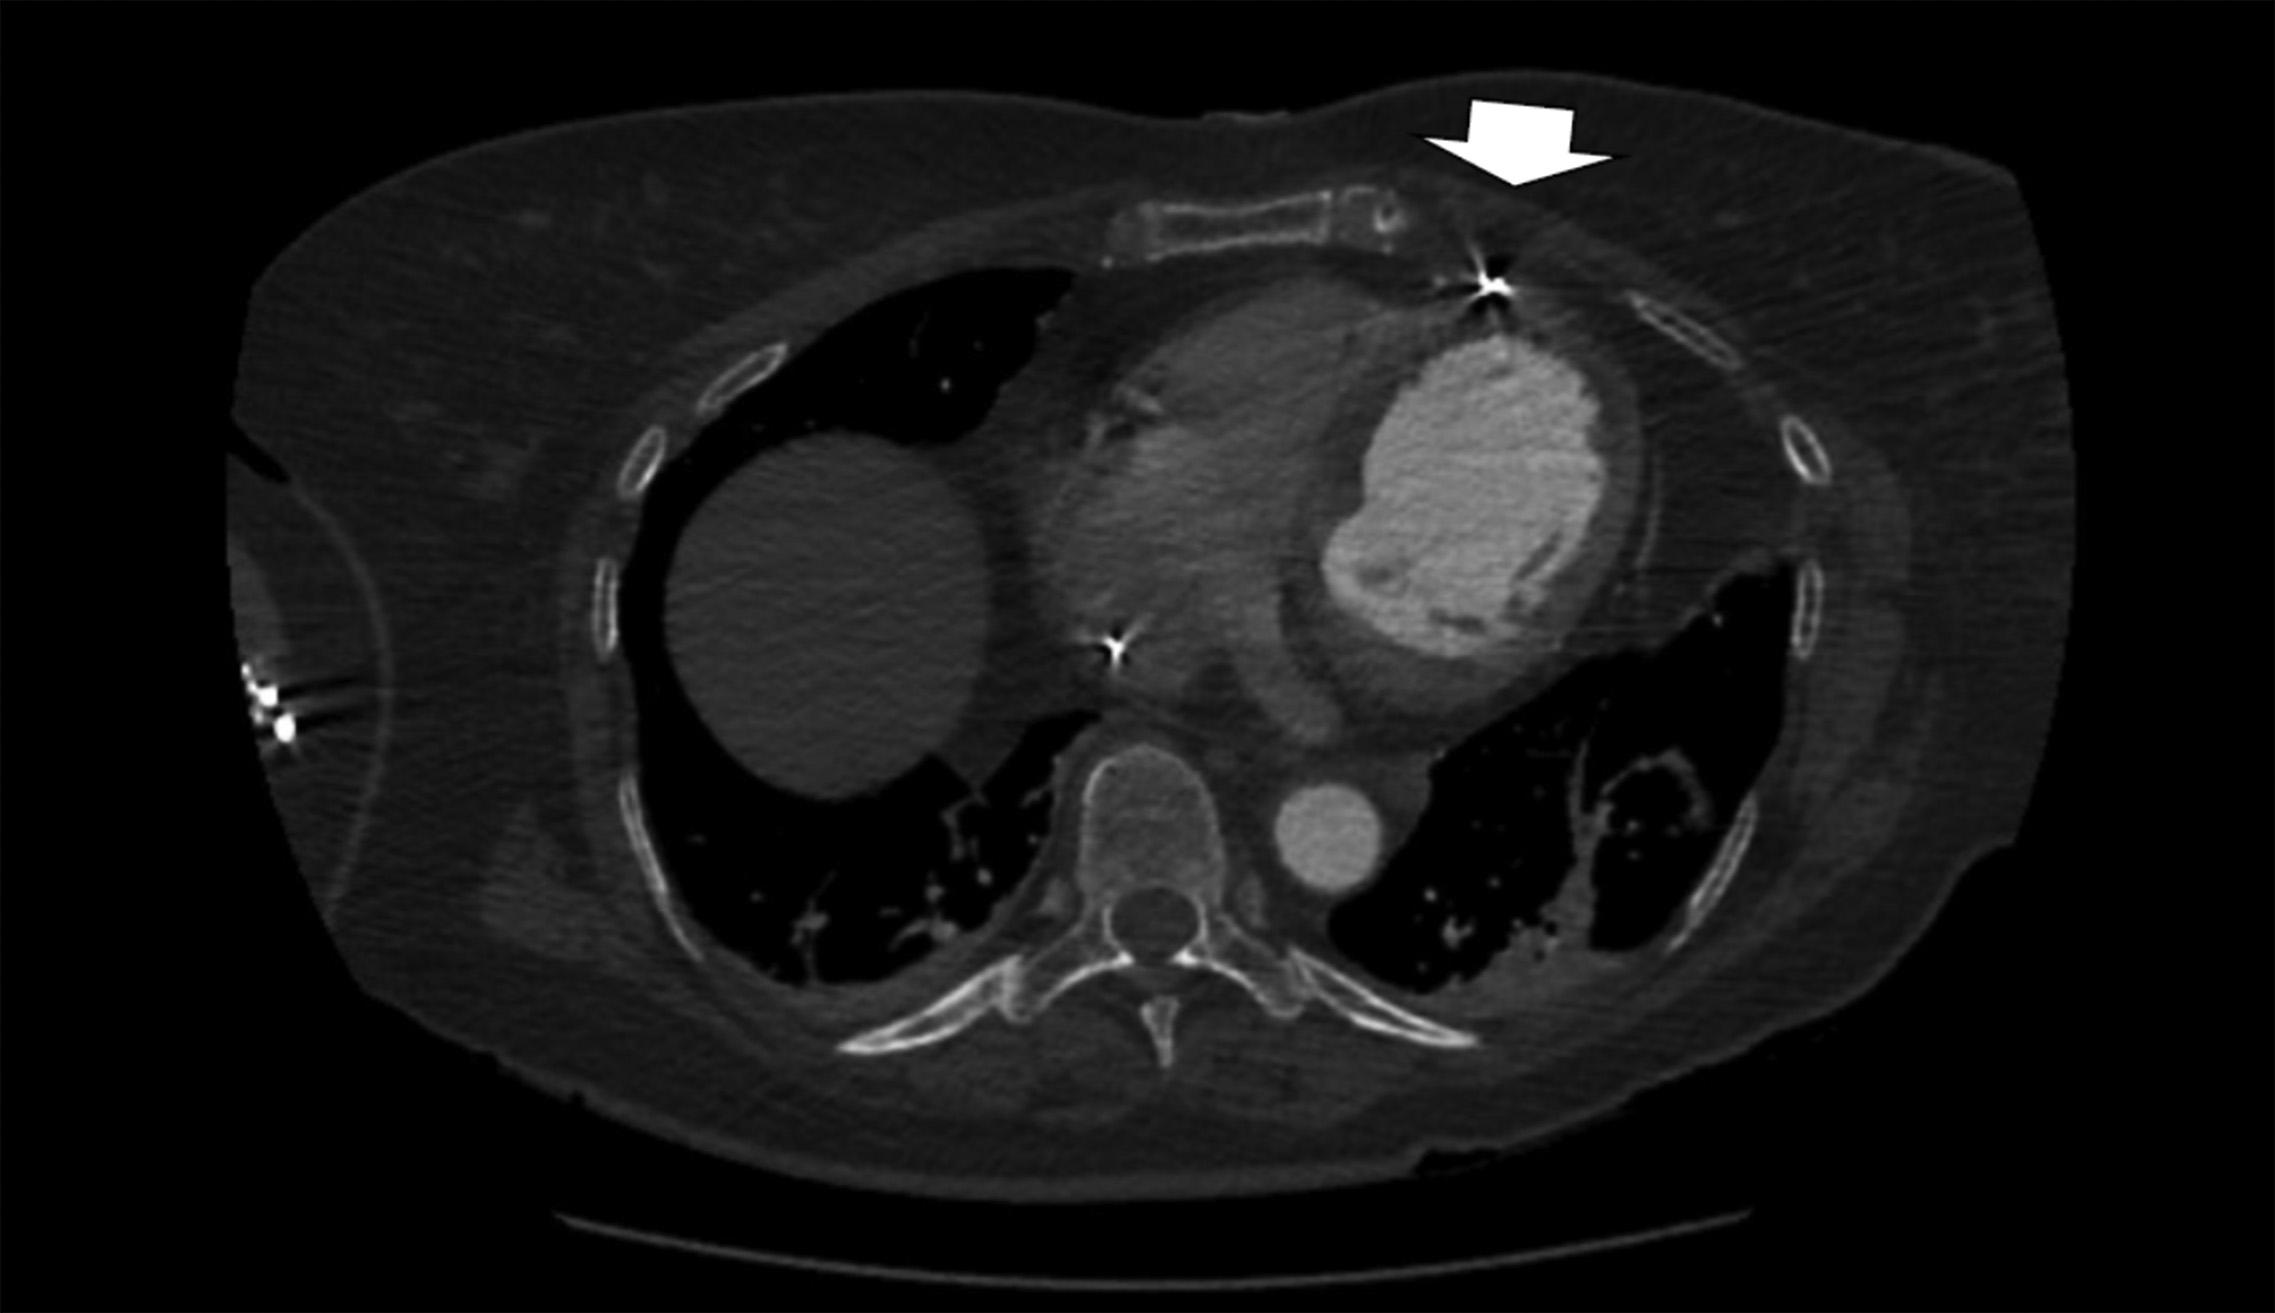

Achestradiograph(CXR)(Image1)showedalargehiatal herniawithtracebilateralpleuraleffusionsanddisplacement ofthegastricbubbletotheright.Computedtomography (CT)withcontrastofthechest/abdomen/pelvis(Images2 and 3)demonstratedalargehiatalherniawithmostofthe stomachinthechest,associatedvolvulus,bilateralpleural effusions,rightgreaterthanleft,andacomplex,partially fluid-filledcollectionalongtheposterioraspectofthehiatal

Anterior-posteriorchestradiographdemonstratinglarge hiatalherniawithdisplacementofthegastricbubble(arrow)from lefttoright.

Image3. Transverseviewofcomputedtomographyofthechest/ abdomen/pelviswithanarrowindicatingpartially fluid-filled collectionposteriortoalargehiatalherniasuspiciousfor esophagealperforation.

Image1. Image2. Coronalviewofcomputedtomographyofthechest/ abdomen/pelvisshowinglargehiatalhernia(arrow).Thepatientunderwentanexploratorylaparotomy,which confirmedthepresenceofanesophagealrupturenearthe squamocolumnarjunctionandrevealedthepresenceofa gianthiatalherniawithanassociatedupside-downstomach. Surgicalrepairoftheesophagealperforationandgastropexy wasperformed.Thepatientwasadmittedtothesurgical intensivecareunitforatotalof fivedaysduringwhich shehadanepisodeofatrial fibrillationwithrapidventricular responsethatresolvedaftermetoprololanddiltiazem.